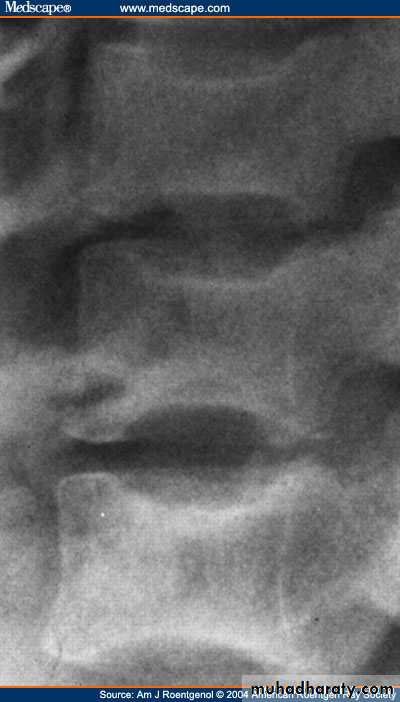

* Rugger jersey spine

rugger jersey spine